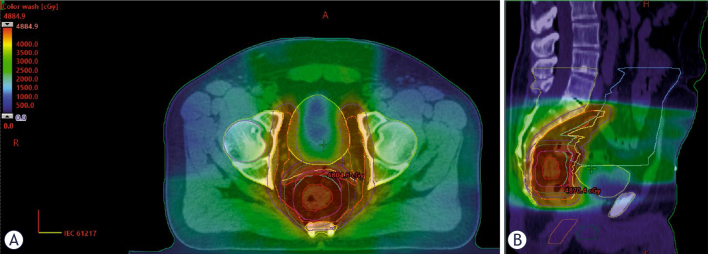

Patients and methods: We analyzed acute hematologic toxicity data from 53 patients who underwent TNT for locally or locoregionally advanced rectal cancer between July 2022 and April 2023. Twenty-eight patients received induction chemotherapy with capecitabine and oxaliplatin [CAPOX], and 25 received consolidation chemotherapy (6 cycles of CAPOX in both groups). The chemoradiation protocol consisted of Volumetric Modulated Arc Therapy with Simultaneous Integrated Boost Radiotherapy (VMAT-SIB RT) up to 48.4 Gy in 22 fractions, concomitantly with capecitabine twice a day (lat. bis in die, BID). The Mann-Whitney U test was performed to compare RIL between the two patient groups. Pelvic bone marrow was contoured as a non-limiting organ-at-risk to assess the received dose, and binary logistic regression was used to determine whether RIL depends on V5Gy~V42Gy or the planning target volume (PTV) size.

Results: Thirty-four patients (64.2%) developed RIL of any grade, which was not significantly associated with either the induction or consolidation chemotherapy TNT regimen (Wald = 3.159, p = 0.076). No significant differences were found in neutrophil counts or the neutrophil-to-lymphocyte ratio. In the logistic regression model predicting the likelihood of RIL, two variables were statistically significant: V10Gy (Wald = 4.366, p = 0.037) and V30Gy (Wald = 6.084, p = 0.014). These results indicate that V10Gy< 71% and V30Gy< 26.6% may reduce the likelihood of developing RIL.

Conclusions: In our study, the sequencing of chemotherapy in TNT for rectal cancer did not predict the development of RIL. However, the incidence of RIL may be reduced by applying RT dosimetric constraints to the pelvic bone marrow.